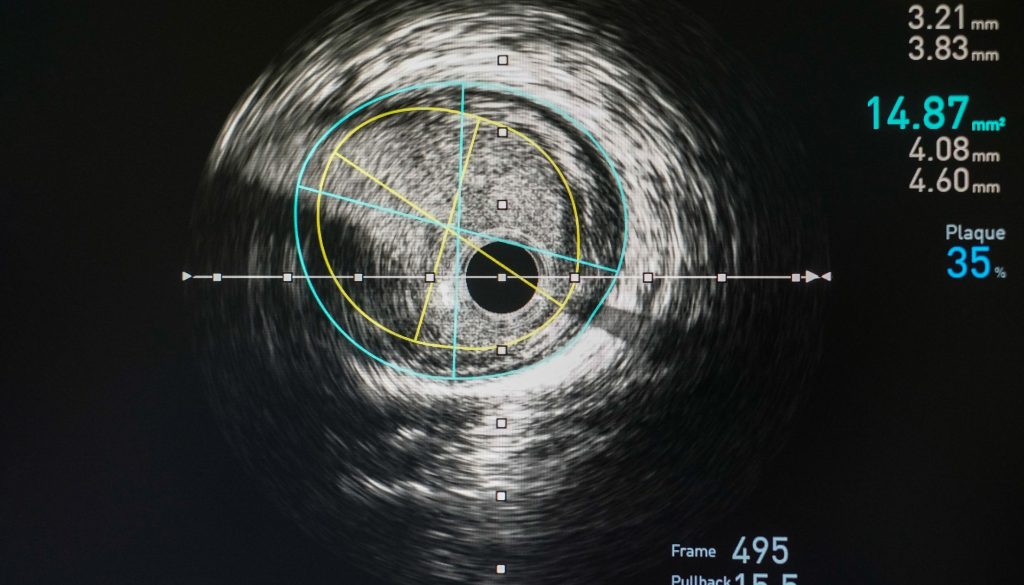

– **الفحوصات التصويرية:** مثل الأشعة السينية أو الرنين المغناطيسي أو التصوير بالموجات فوق الصوتية لتحديد مدى الانسداد.

سيقوم الطبيب بإدخال القسطرة عبر شق صغير ويتم توجيهها بدقة إلى الشريان المستهدف باستخدام تكنولوجيا تصوير متقدمة.